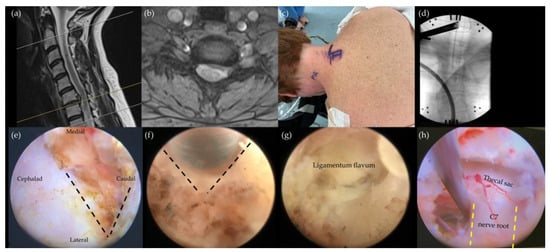

4.3. Cervical Endoscopic Unilateral Laminotomy for Bilateral Decompression (CE-ULBD)

- Carr, D.A.; Abecassis, I.J.; Hofstetter, C.P. Full endoscopic unilateral laminotomy for bilateral decompression of the cervical spine: Surgical technique and early experience. J. Spine Surg. 2020, 6, 447–456. [Google Scholar] [CrossRef] [PubMed]